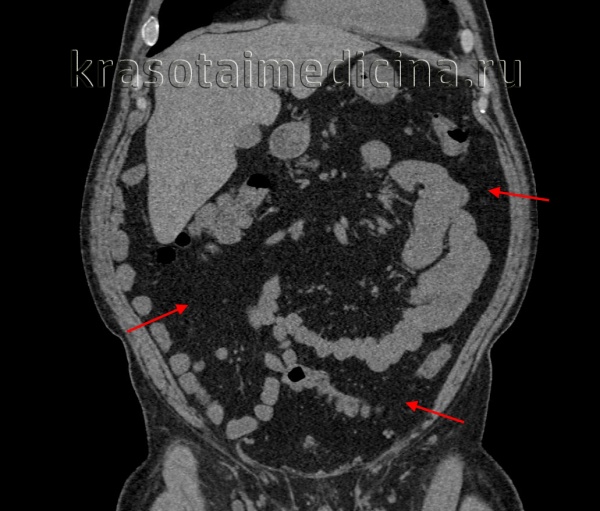

КТ ОБП. Избыточное количество висцеральной жировой клетчатки у пациента с повышенным индексом массы тела.

КТ ОБП. Избыточное количество подкожной жировой клетчатки живота (красная стрелка), висцеральной клетчатки (синяя стрелка), жировой гепатоз (зеленая стрелка).